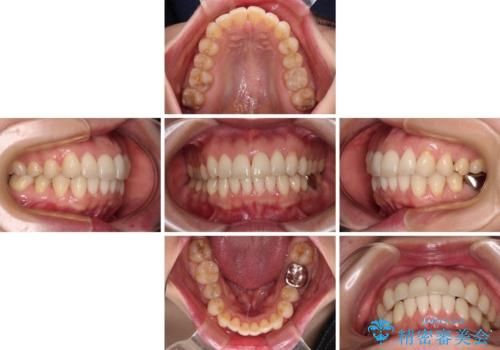

- 上下の前歯のデコボコを気にして来院された患者様です。

妊娠中であり、途中通院が難しくなる可能性があることから、インビザラインによる矯正治療を行うこととしました。

上下顎歯列全体の後方移動とIPR(歯と歯の間を削る)によってデコボコが解消するように設計しました。